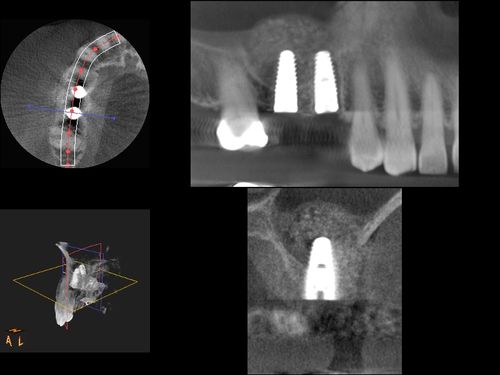

dental implants

Dental implants do more than replace missing teeth—they help you eat, speak, and live with total confidence. At Epperson Payne Dental Group, we combine expert care with the latest technology to deliver results that last.

Getting dental implants is a big decision, and you deserve the absolute best care. Our practice brings everything you need together in one place - from detailed planning to expert surgery to the final artistic touches that make your smile look natural and beautiful.

We combine the latest technology with deep experience in implant dentistry to deliver results you'll love. Whether you need to replace one tooth or restore your full smile, our team focuses on getting every detail right, giving you a comfortable experience and lasting results you can count on.